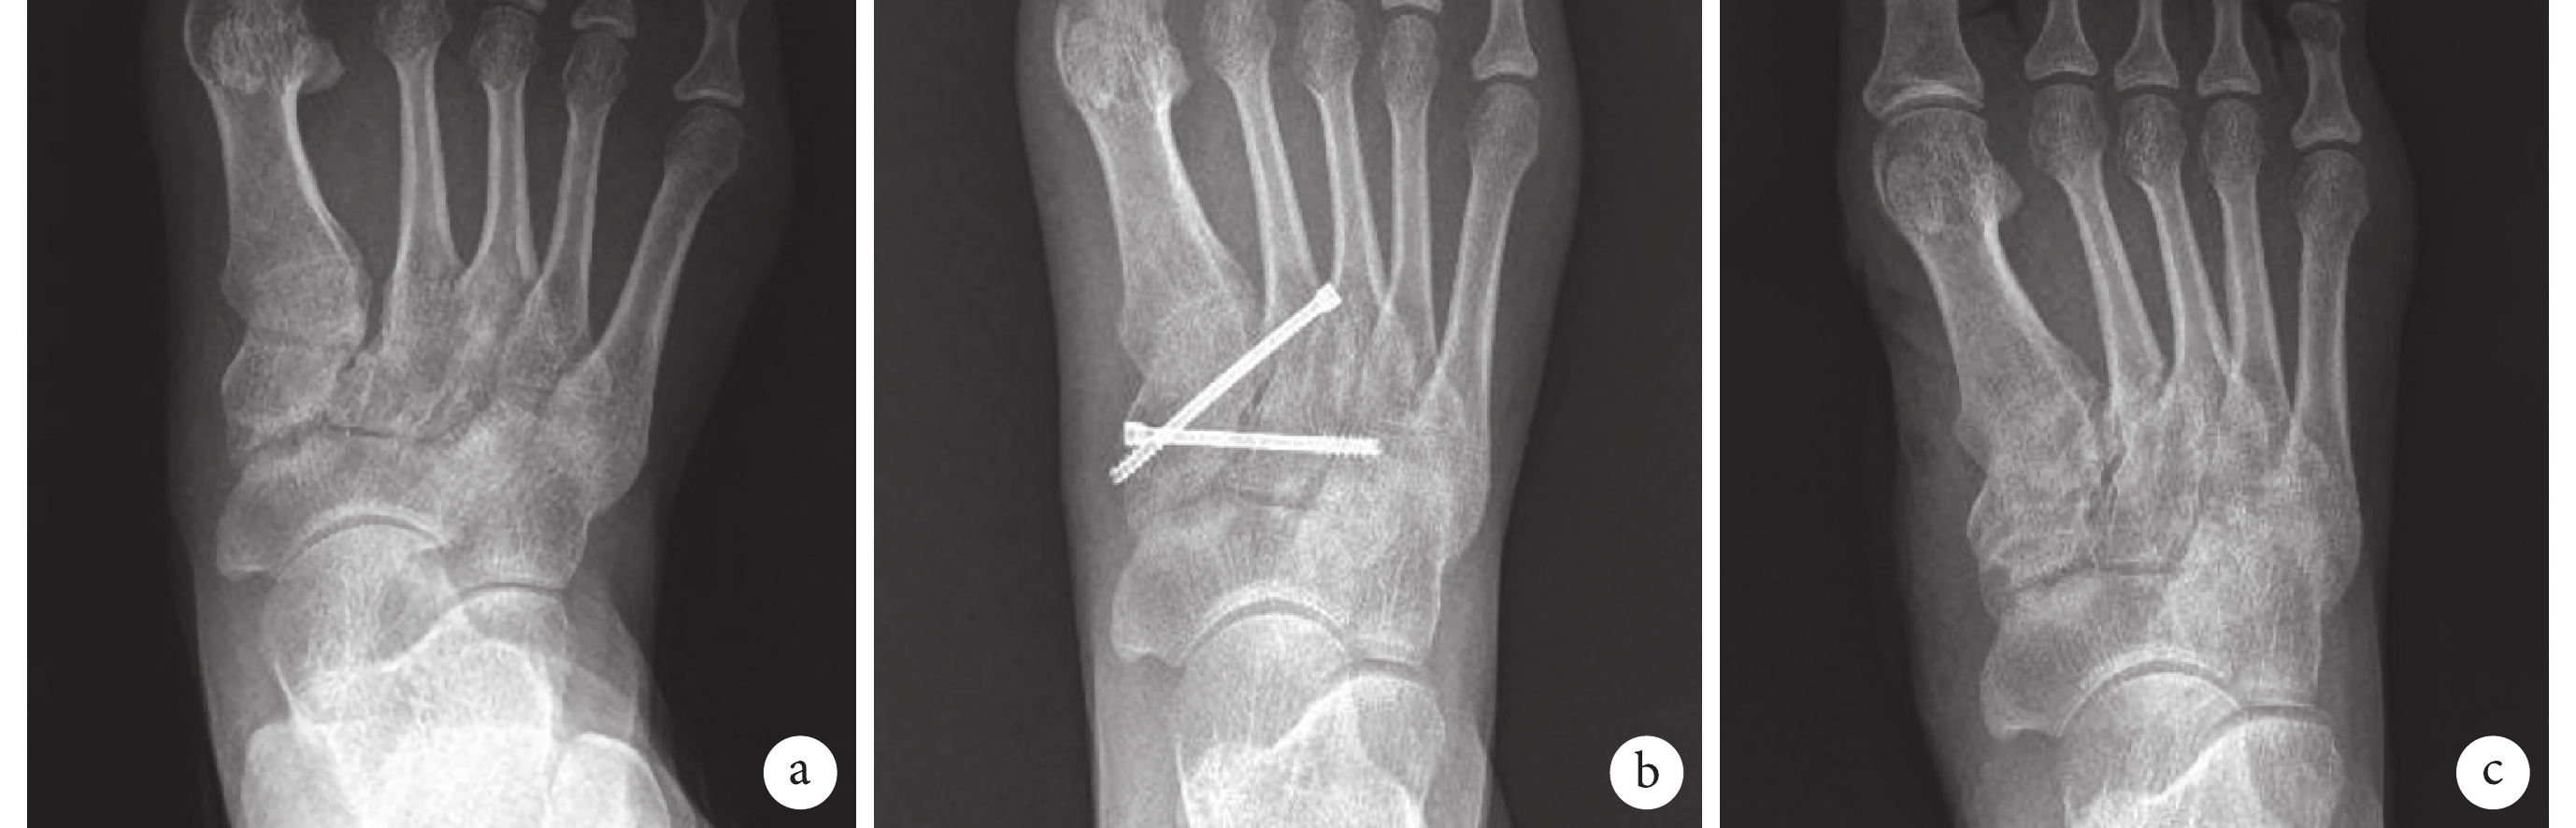

X 線片復查示,隨訪期間未見關節間隙變窄、軟骨下骨囊腫形成或軟骨下骨硬化等關節炎表現以及中足塌陷,無內固定失效及復位丟失發生。見圖1、2。術后 9~24 個月 20 例患者(新鮮組 11 例、陳舊組 9 例)二次手術取出內固定物,平均取出時間為 14.5 個月。

a. 術前;b. 術后 3 個月;c. 術后 1 年

Figure1. X-ray films of a 25-year-old female patient with left occult Lisfranc injury in acute groupa. Before operation; b. At 3 months after operation; c. At 1 year after operation